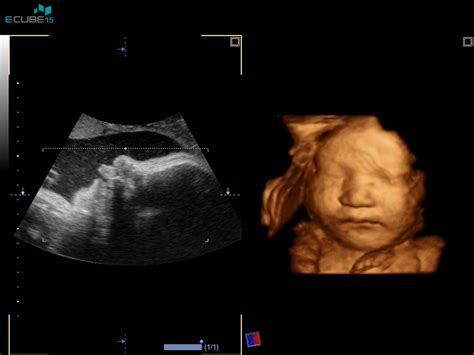

Nuhalna svetlina je strokovni izraz za debelino nabrane tekočine pod kožo v zatilju ploda. Ta meritev se opravi med ultrazvočnim pregledom, ki običajno poteka preko trebušne stene nosečnice (transabdominalni ultrazvok). Le v redkih primerih, ko položaj ploda ali druge okoliščine to narekujejo, je potreben pregled skozi nožnico (transvaginalni ultrazvok). Da bi zagotovili natančnost meritve, je ključno, da je plod v pravilni legi, kar lahko vpliva na trajanje pregleda. Pred posegom se nosečnico prosi, da popolnoma izprazni svoj mehur, kar omogoča boljšo vizualizacijo.

Meritev nuhalne svetline je časovno omejena in mora biti opravljena med 11. tednom 0 dnevi nosečnosti (ko je dolžina ploda približno 45 mm) in 13. tednom 6 dnevi nosečnosti (ko plod doseže dolžino okoli 84 mm). V tem obdobju se namreč značilnosti nuhalne svetline najbolj jasno izražajo in omogočajo najzanesljivejše ocenjevanje tveganja.